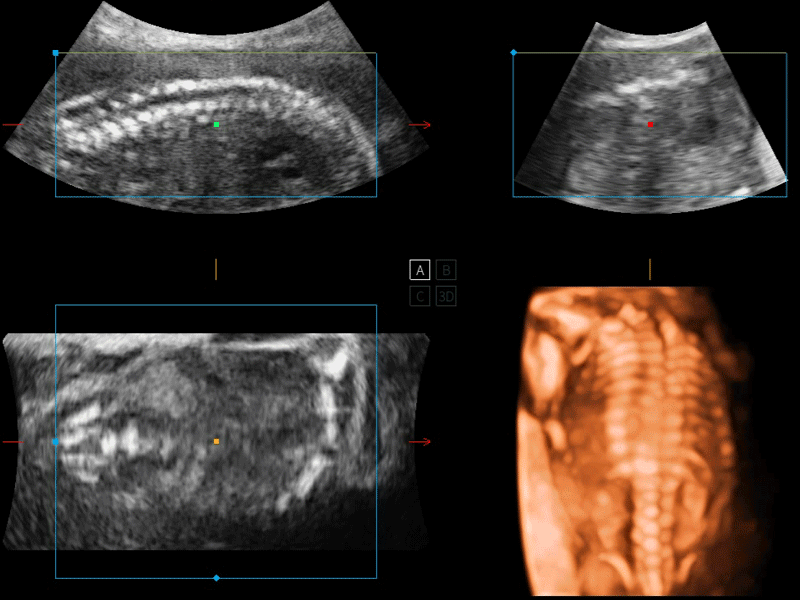

临床图像

S-Live 高分辨率容积成像

通过仿真成像技术对3D/4D立体数据进行渲染,多种初始光源位置可选,并支持轨迹球360°光源位置自由调节,清晰显示不同方位容积图像细节。

S-Fetus 产科扫查助手

S-Fetus基于大数据深度学习算法,能够帮助您在产前筛查过程中智能识别胎儿标准切面、自动测量并录入报告。一个按键,即可智能、精准、高效地获取胎儿生理指标,极大简化您的产科检查操作。